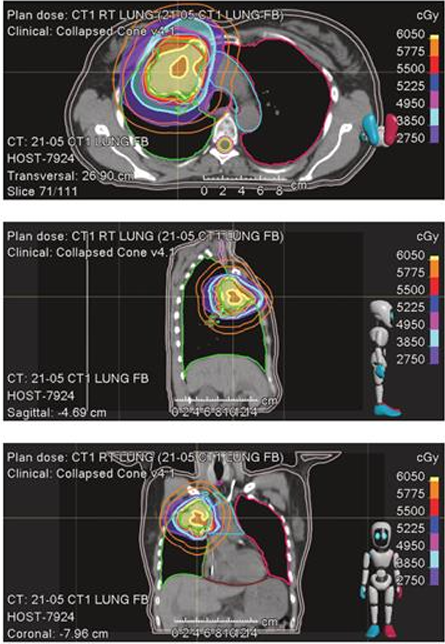

2021年5月,患者因右肺上叶主结节出现孤立性进展,接受立体定向放射治疗(SBRT),剂量为55Gy,分10次照射。治疗后,无进展生存期(PFS)达12个月,展示局部巩固治疗在控制寡进展中的有效性。然而,2022年6月,患者在维持免疫治疗期间,右肺下叶和左肺下叶出现新病灶,接受SBRT治疗,剂量分别为62.5Gy(分10次)和50Gy(分5次,每次10Gy,隔日一次)。同年7月,患者出现左额叶脑转移,经手术切除后,接受SBRT至切除腔,剂量为27Gy(分3次),每次9Gy。这表明,对于寡转移病灶,局部巩固治疗能够有效延长患者的PFS。